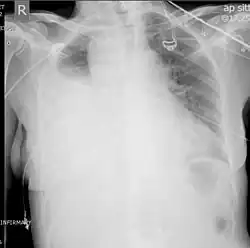

Chest X-ray showing left sided hemothorax (arrowed)

Two chest X-rays: left showing a massive left-sided hemothorax; right showing a massive right hemothorax

A chest X-ray is the most common technique used to diagnosis a hemothorax.[23] X-rays should ideally be taken in an upright position (an erect chest X-ray), but may be performed with the person lying on their back (supine) if an erect chest X-ray is not feasible. On an erect chest X-ray, a hemothorax is suggested by blunting of the costophrenic angle or partial or complete opacification of the affected half of the thorax. On a supine film the blood tends to layer in the pleural space, but can be appreciated as a haziness of one half of the thorax relative to the other.[5] A small hemothorax may be missed on a chest X-ray as several hundred milliliters of blood can be hidden by the diaphragm and abdominal viscera on an erect film. Supine X-rays are even less sensitive and as much as one liter of blood can be missed on a supine film.[24]